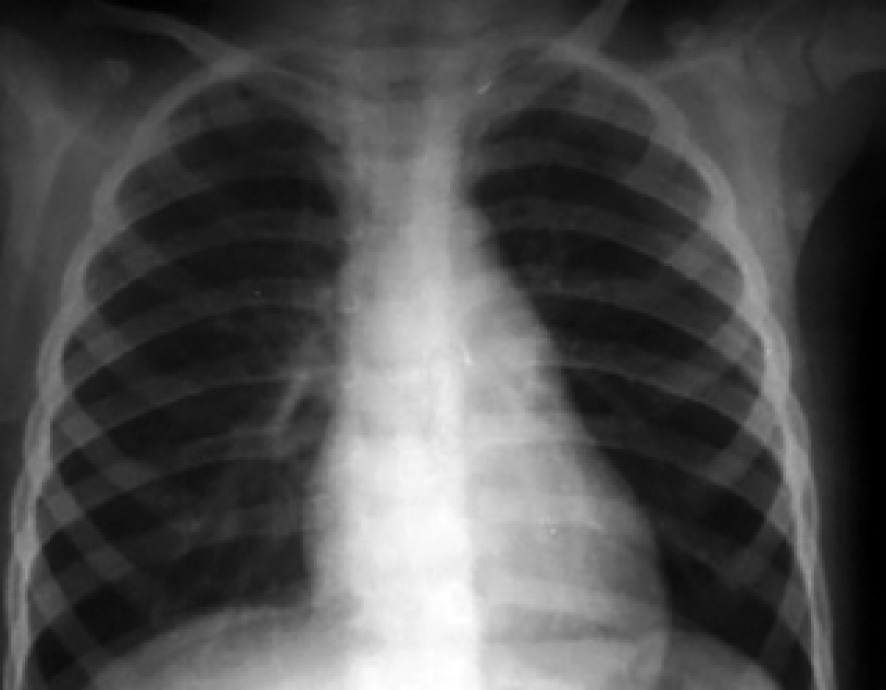

На рентгенограммах органов грудной клетки, выполненной в условиях реанимации, выявлены очаги инфильтрации в 8-м, 9-м, 10-м сегментах правого легкого и 8-м, 9-м сегментах левого легкого (рис. 6).

Рис. 6. Рентгенограмма органов грудной клетки в положении лежа на спине при поступлении в стационар